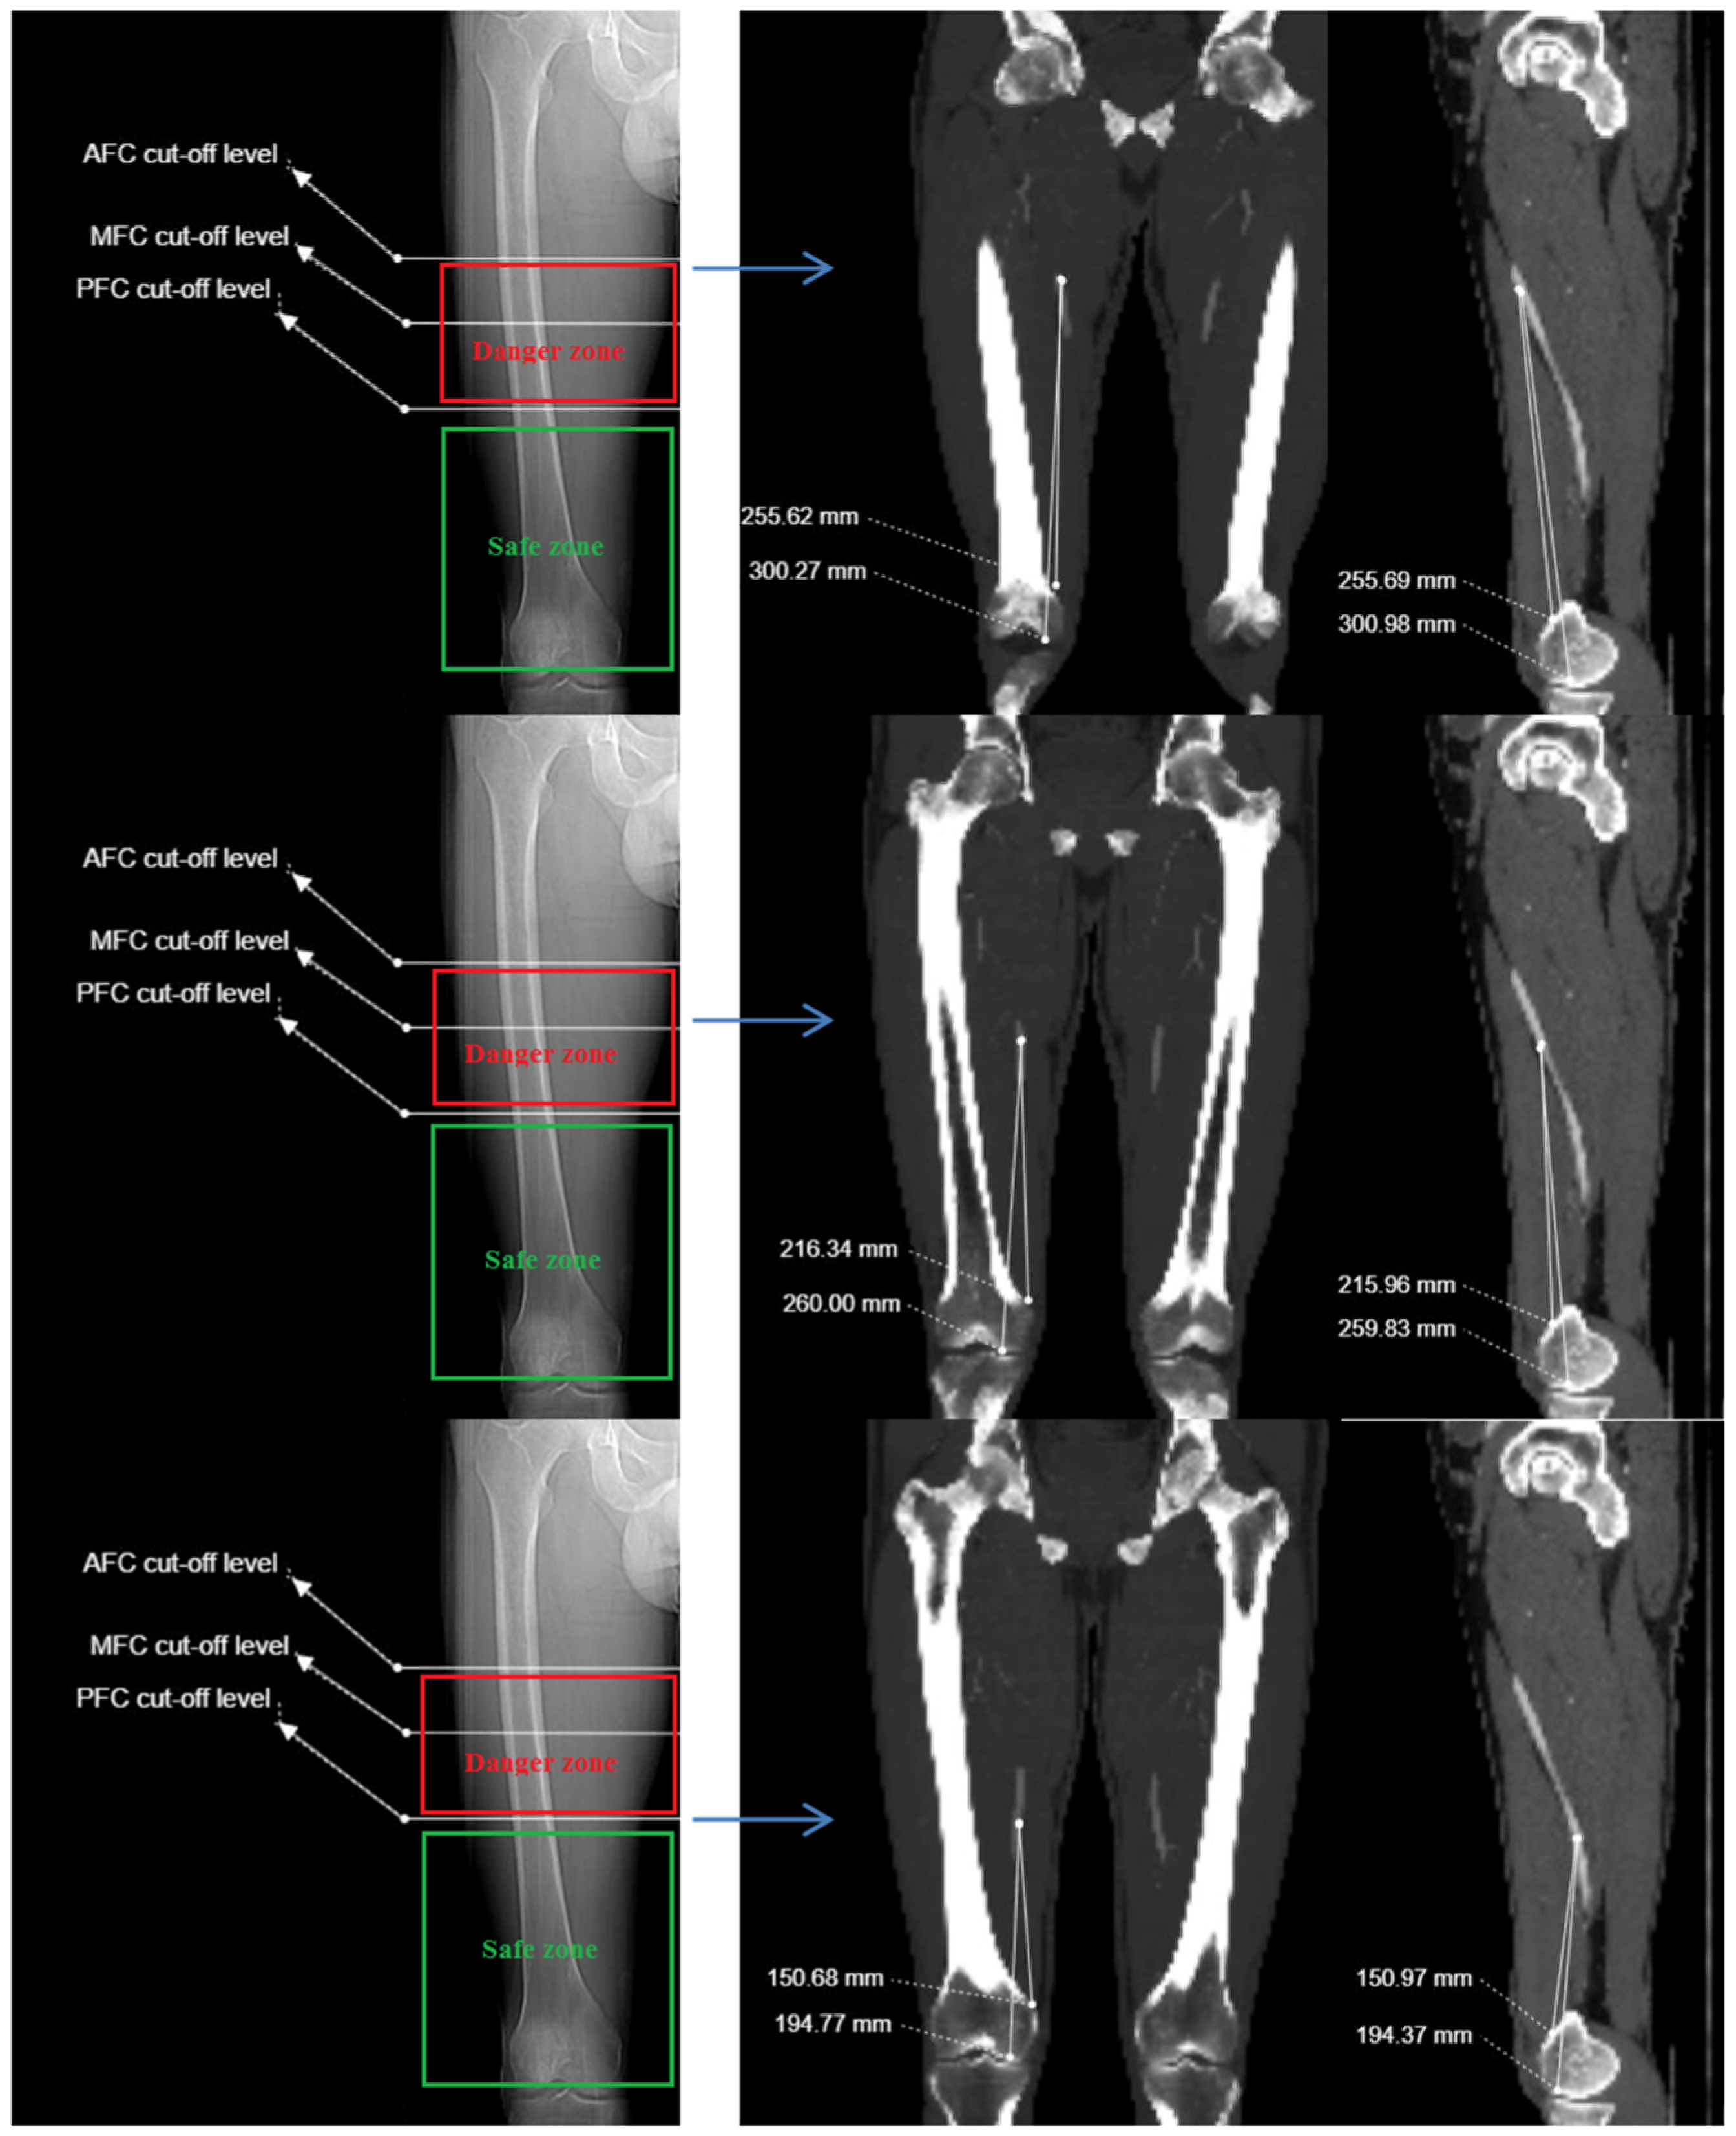

2.3. Imaging and Measurement Methods

| Anterior femoral cortex | 223.01 ± 27.38 (156.3–293.8) | 265.04 ± 28.21 (207.0–334.5) | 27.20 ± 5.32 (15.1–40.4) | 16.49 ± 9.94 (−9.7–40.5) |

| Midsagittal femoral cortex | 180.78 ± 26.83 (107.1–246.3) | 222.40 ± 27.65 (156.1–292.6) | 25.22 ± 5.52 (11.5–58.2) | NA |

| Posterior femoral cortex | 128.01 ± 29.59 (54.1–200.1) | 170.13 ± 29.96 (93.9–241.7) | 22.93 ± 6.04 (7.6–38.0) | −36.58 ± 11.30 (−79.2–−10.3) |

| Distance between SFA and AT at level of AFC | 160 | 223.0 ± 27.3 | 0.568 ** | 0.000 | 0.535 ** | 0.000 |

| Distance between SFA and AT at level of MFC | 160 | 180.7 ± 26.8 | 0.464 ** | 0.000 | 0.437 ** | 0.000 |

| Distance between SFA and AT at level of PFC | 160 | 128.0 ± 29.5 | 0.244 ** | 0.000 | 0.217 ** | 0.000 |